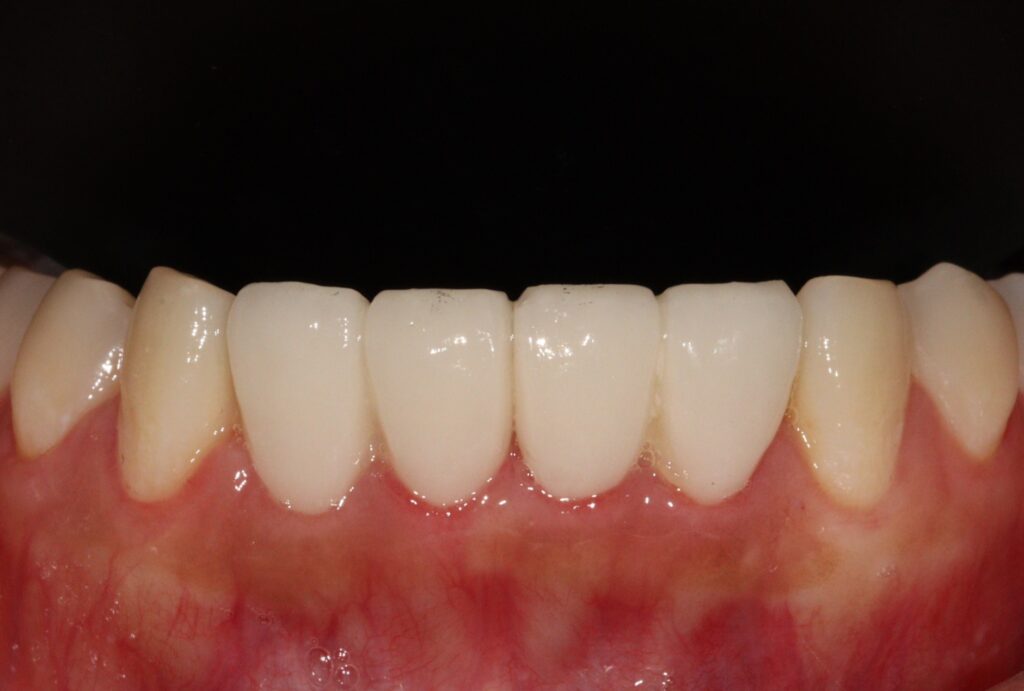

모두 신경치료 후 크라운을 싱글로 제작하였습니다.

잇몸치료 후 회복시간을 두고 PMMA 프로비저널 크라운으로

환자분의 심미적 요구도를 확인해서

최종보철에 반영하였는데요.

빠르게 문제 없이 최종 보철까지 마무리 되어

환자분께서도 매우 만족하셨습니다.